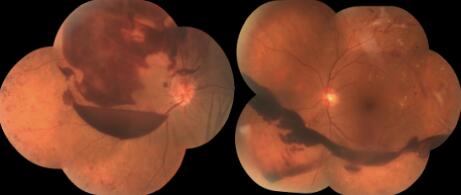

5.視網膜?糖尿病病程在5年以下者糖尿病性視網膜病變的發生率為28%;6~10?年者為36.4%?;11~15年者為58%;15年以上者為72.7%。初期可無眼部自覺癥狀,病情發展可出現視力下降,視網膜有微血管瘤、出血、滲出。小血管破裂,出血進入玻璃體內,量少則眼前有黑影,大量出血進入玻璃體內時視力可嚴重下降,甚至失明。出血機化后牽拉視網膜可引起繼發性視網膜脫離。因此2型糖尿病患者,在確診糖尿病時就應該進行眼底檢查;1型糖尿病患者在青春期前或青春期發病,可在12歲開始眼底檢查,青春期后發病患者一旦診斷即進行眼底檢查;妊娠糖尿病,在妊娠前或妊娠初3個月首次進行眼底篩查。三種類型的糖尿病均根據眼底檢查的結果,聽從醫生的建議定期檢查眼底,一旦需要視網膜激光光凝治療,應積極完成全視網膜激光光凝,如果錯過視網膜激光光凝時間,出現大量玻璃體積血及視網膜脫離(如下圖),則只能行玻璃體切除手術治療。?